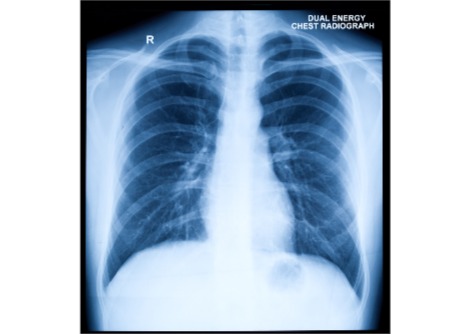

تَظهر الجلطات عادةً في الساقين ، وغالبًا ما تبدأ في أحد الأوعية الدموية في ربلة الساق . التورم والألم والاحمرار من الأعراض الشائعة . نادرا ما تكون الجلطات خطيرة إذا تم علاجها مبكرًا. ومع ذلك ، إذا انفصلت إحداها  ، ووصلت إلى الرئتين في مجرى الدم ، والتصقت بجدار الوعاء الدموي هناك ، فقد يكون "الانصمامُ الرئويُ" الناتجُ  مهددًا للحياة   .

يتضح من النتائج ، المنشورة الآن في مجلة الطب الباطني ، أن مؤشر كتلة الجسم في سن 8 و 20 ، بشكل مستقل عن بعضهما البعض ، يمكن ربطه بجلطات الدم الوريدية . قد تحدث هذه ، على سبيل المثال ، الساق (تجلط الأوردة العميقة ، DVT) أو الرئة (الانصمام الرئوي)..